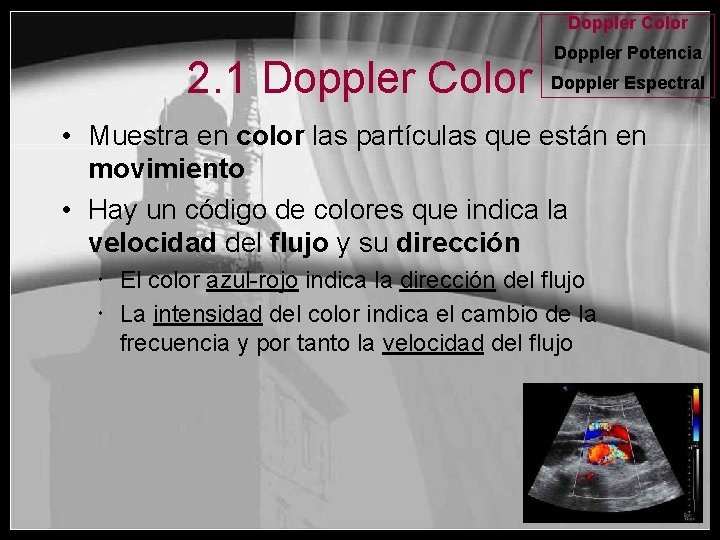

Doppler Color 2. 1 Doppler Color Doppler Potencia Doppler Espectral • Muestra en color las partículas que están en movimiento • Hay un código de colores que indica la velocidad del flujo y su dirección El color azul-rojo indica la dirección del flujo La intensidad del color indica el cambio de la frecuencia y por tanto la velocidad del flujo